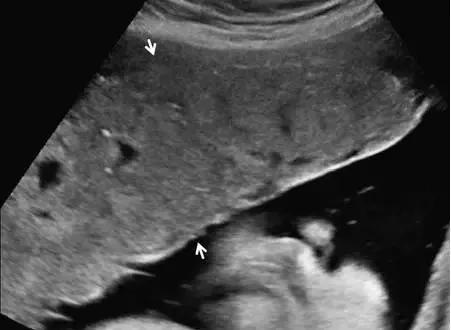

超声最早可在孕 6 周(经阴道超声)或孕 10 周(经腹部超声)显示出胎盘,表现为妊娠囊周围的薄层环状高回声。妊娠 12~13 周时,多普勒超声可显示绒毛血流。孕 14~15 周时,胎盘已充分发育,表现为显著的高回声。此时,也可看到由蜕膜、肌壁、子宫血管等组成的胎盘后复合体(图 1)。

图 1 孕 12 周时的正常胎盘矢状面,其后可见低回声的胎盘复合体(小箭头)